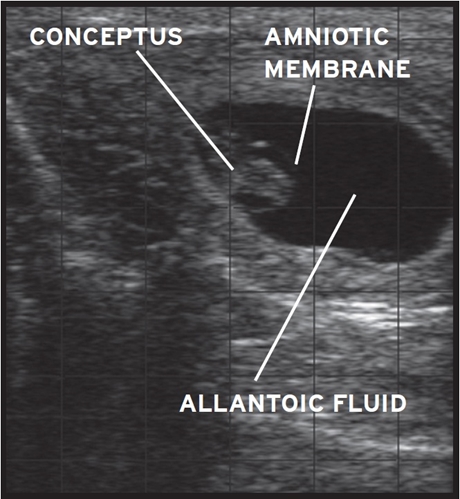

PALPACIÓN DEL CONCEPTUS

El conceptus es la fase de la formación del embrión durante la migración embrionaria alrededor del día 14 de gestación.

El signo positivo es la membrana fetal deslizable, MFD, que se puede percibir desde los 28 días. Para ello, usando la técnica de palpación con cambio de posición de la mano, desplazaremos los dedos a través de los cuernos uterinos, sintiendo una tercera estructura.

La palpación en el cuerno uterino grávido debe hacerse en el borde a nivel de la bifurcación y realizar una ligera presión para notar el desplazamiento de la membrana placentaria y una leve presión en el cuerno para sentir el líquido del conceptus.

Las paredes de los cuernos están delgadas y se siente la presencia de líquido, éste es el síntoma de preñez.